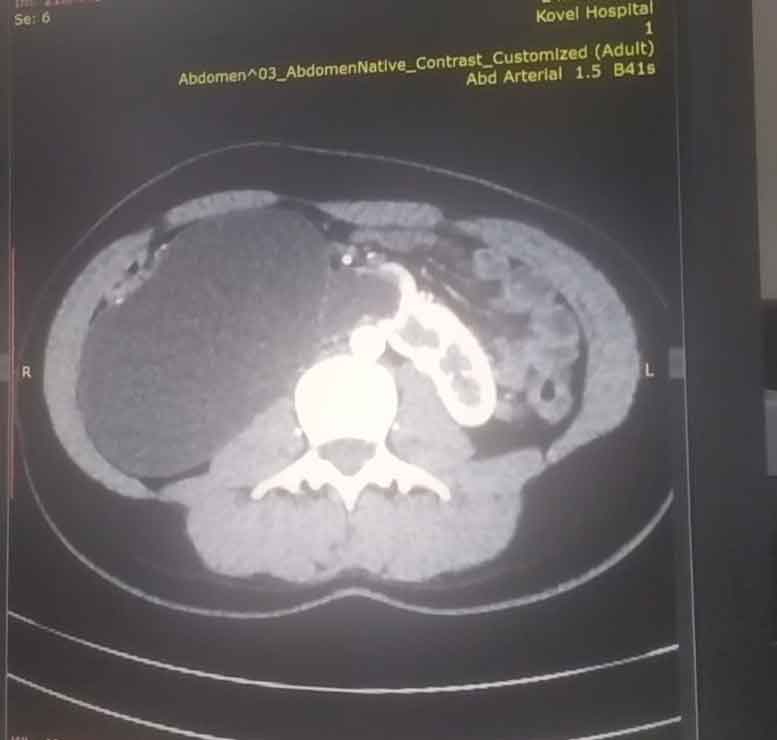

17-річна пацієнтка мала вроджену ваду сечовидільної системи - підковоподібну нирку (зрощення двох нирок). Стан її здоров’я погіршувався упродовж багатьох років, аж поки права половина підковоподібної нирки перестала функціонувати, - повідомляє Ковельське МТМО у Фейсбук

Хвору доставили в лікарню у важкому стані з вираженим больовим синдромом та наявністю гіпертонічного кризу. Через звуження у сечоводі та ускладнення відтоку сечі, об’єм рідини в нирці сягнув критичного рівня. А збільшення її розмірів стало помітним навіть зовні.

Лікарі діагностували термінальний гідронефроз із наслідками, гідронефротичну трансформацію правої половини підковоподібної нирки, вторинну артеріальну гіпертензію.